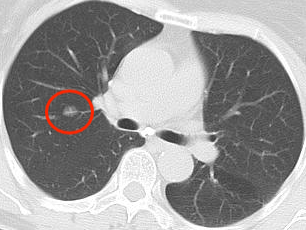

近年来,贵州航天医院各科室紧跟医学前沿,不断强技术、补短板,大力开展新技术、新项目,完成了许多高精尖、高难度、本地区“首例”的技术,填补了医院医疗技术空白,满足了群众日益增长的医疗需求。 贵州航天医院呼吸与危重症医学科是贵州省内呼吸疾病治疗规模最大,诊疗项目最全的呼吸疾病品牌科室,呼吸介入技术达到了全国先进水平,在贵州省内处于领先的地位。 本期,我们将为大家带来呼吸与危重症医学科特色技术——氩氦刀冷冻消融技术治疗肺癌、高危肺结节。 案例分享 患者在体检时发现右肺结节(10mm),就诊于当地我院一专科联盟合作医院,但因当地医疗条件有限,患者通过专科联盟绿色通道前往我院就诊,入院后,通过经皮肺穿刺活检,病理诊断为右肺原位腺癌,科室立即组织专家开展肺结节多学科会诊(MDT),为患者制定诊疗方案。 经充分的沟通下,患者及家属拒绝手术切除。科室再次严格讨论评估,患者情况满足氩氦刀冷冻消融术指征,再次将治疗方案与患者及家属沟通同意后,为患者制定并成功实施氩氦刀冷冻消融术。 冷冻消融术中 术后,患者定期复查,恢复效果良好。 术前 术后即刻 术后1月(反应性增大) 术后6月(纤维条索) 术后12月(纤维条索变细) 什么是氩氦刀冷冻消融技术 氩氦刀冷冻消融技术是一种先进的微创超低温冷冻消融肿瘤的医疗技术,它利用氩气和氦气的快速温度变化特性,实现对病变组织的精准冷冻和复温,以达到消融和破坏肿瘤细胞的目的。 氩氦刀冷冻消融技术原理 氩氦刀冷冻消融技术基于焦耳-汤姆逊效应,通过氩气和氦气的快速交换实现局部组织的超低温冷冻(-140℃到-190℃)和快速复温(20℃到45℃),当氩气通过金属杆尖端的蒸发器时,其气压突然降低,会大量吸收周围的热量,使金属杆尖部的气温迅速下降到超低温;随后,氦气在极短的时间内使组织迅速复温,通过热胀冷缩的原理,使肿瘤细胞爆裂。 (一)直接杀伤( 靶区冷冻消融效应) 1.快速冷冻(降温段):细胞内冰晶快速生长并撕裂细胞,导致细胞损坏。 2.慢速冷冻(低温段):细胞外冰晶生长导致水渗出细胞,造成细胞脱水。 3.升温:水迅速进入细胞,导致细胞涨破。 (二)间接杀伤( 冷冻的血管栓塞效应) 病灶区域快速冷热交替,引起微血管细胞脱水、蛋白质变性、微血管损伤、 冰晶及微血栓在微血管内形成,导致血小板聚集、血管栓塞, 局部细胞缺血坏死。 (三)抗肿瘤免疫( 冷冻免疫激活效应) 随着肿瘤细胞的破裂和坏死,促使肿瘤免疫调节因子停止分泌,逆转免疫抑制状态;可调控表面抗原,促进淋巴细胞增殖,提高身体抗肿瘤免疫能力。 氩氦刀冷冻消融技术优势 (一)精准度高:通过精确的靶点定位和温控技术,可实现对病变组织的精准冷冻和复温,避免损伤正常组织。 (二)微创治疗:对周围正常组织的热损伤小,无需开胸开腹,仅有一个针孔,恢复快,几乎无疤痕。 (三)适应症广:肺腺体前驱病变(癌前病变)、甲状腺结节、乳腺结节等;多原发磨玻璃肺结节,因各种原因不适合手术的早期肺癌、肝癌等;内科治疗无法控制的少发转移瘤等。 (四)可重复治疗:由于冷冻治疗对身体的创伤和痛苦较小,可以多次重复进行治疗,这对巨大的肿瘤和多发的肿瘤尤其适用。 (五)无毒性:冷冻治疗是以物理方法杀灭肿瘤,不向体内注射任何药物,避免外科手术、化放疗等对身体带来的巨大创伤和毒副作用,能有效减轻患者肿瘤负荷和痛苦,因此与化放疗、分子靶向药物等治疗方式相比属于无毒治疗。 氩氦刀冷冻消融技术对于早期肺癌、高危结节,可作为手术的替代治疗。对于晚期较大的肿瘤可作为姑息治疗,增强综合治疗的效果,可减少肿瘤负荷,减轻症状,提高生活质量,延长生存时间。 近年来,随着医学影像技术发展和肺癌筛查的广泛开展,肺内结节的检出率显著提高。无论肺内磨玻璃结节还是实性结节,单发或多发,都需要引起重视,定期复查,动态观察结节变化,如有需要请积极治疗。 贵州航天医院 呼吸与危重症医学科专家团队 廖江荣 国务院政府特殊津贴专家、遵义市呼吸疾病临床医学中心学科带头人、二级教授、主任医师 学术任职: 亚洲冷冻治疗学会副主席 第二届中国医药教育协会介入微创专业委员会呼吸分会副主任委员 中国抗癌协会肿瘤微创治疗专业委员会常务委员 中国防痨协会结核病转化医学专业分会常务委员 第一届中国人体健康科技促进会呼吸介入专委会常务委员 中国医疗保健国际交流促进会结核病学分会第三届委员会常务委员 中国抗癌协会肿瘤微创治疗专业委员会粒子治疗学组第四届委员会委员 中国结核病防治综合质量控制专家指导委员会委员 “西部呼吸介入联盟”副理事长 专业擅长: 呼吸系统(肺)疑难病的诊断及危重病的抢救,呼吸系统(肺)感染性、疑难性疾病介入快速诊断(ROSE),尤其在肺癌、肺小结节早期诊断,肺癌微创综合靶向治疗,难治性、复治性、重症肺结核诊疗,硬质支气管下复杂性气道狭窄诊治,纤支镜介入治疗气道肿瘤、结核、气道狭窄(球囊扩张、支架植入、高频电刀、氩气刀、冷冻、灌洗、注药、微波消融),间质性肺疾病的诊疗上具有极高水平;带领团队勇于创新,在贵州省率先开展多项新技术、新疗法,如CT引导下及纤支镜下I125粒子植入及CT引导下微波、冷冻消融介入治疗肺癌等多项新技术,带动了贵州省肺部疾病的介入治疗水平提高。 唐永江 四川大学华西医院 呼吸与危重症医学科 副主任医师 呼吸危重症医疗组长 香港中文大学博士 美国康奈尔大学访问学者 贵州航天医院 呼吸与危重症医学科 学科带头人 主要从事呼吸危重症(特别是呼吸重症感染)的临床及科研工作。 PCCM专培结业医师 中华医学会呼吸病学分会呼吸危重症学组秘书 中华医学会呼吸病学分会ECMO工作组成员 四川省医学会呼吸病学专委会介入学组委员兼秘书 发表文章20余篇,主持及参与多项国家自然科学基金及省卫健委基金。 蒋 婷 呼吸、感染党支部书记,呼吸与危重症医学科主任,副主任医师 专业擅长:从医20余年,在呼吸系统疾病、介入呼吸病学、肺部结核、肺部肿瘤等方面具有丰富的临床经验和专业技能,尤其是慢性阻塞性肺疾病、支气管扩张、肺结核、耐药肺结核、肺癌、胸腔积液等肺部疾病的诊治、微创介入、危重病患者抢救。 现任中国防痨协会人兽共患结核病专业分会委员,中国女医师协会第一届介入专业委员会委员,贵州省基层呼吸疾病防治联盟-间质性肺疾病联盟委员,贵州省防痨协会第七届理事会理事,贵州省中西医结合学会呼吸专业委员介入呼吸病学组委员,贵州省遵义市中医药学会中西医结合肺病(呼吸)分会副主任委员,贵州省遵义市中医药学会中医肿瘤专业委员会常委;发表论文数篇,参与并主持多项科研项目。 王 云 中共党员,呼吸与危重症医学科一病区副主任,副主任医师 专业擅长:擅长呼吸系统常见病及疑难危重症、介入呼吸病学、肺部肿瘤疾病的诊治,尤其擅长快速现场评价(ROSE)技术。 贵州省中西医结合学会呼吸专业委员会介入呼吸病学组委员,遵义市中医药学会中西医结合肺病(呼吸)分会委员,贵州省中西医结合学会第六届呼吸专业委员会委员。 李桂凤 中共党员,呼吸与危重症医学科三病区主任,副主任医师 专业擅长:从事呼吸系统疾病、结核病学、介入呼吸病学、肿瘤综合治疗、呼吸康复等临床工作20余年,擅长呼吸内科常见病、多发病及疑难重症危重病症的诊治,尤其对重症疑难结核及耐药结核病、介入治疗(肺)呼吸系统疾病、呼吸危重病抢救等方面具有较高诊疗水平。 中国防痨协会非结核病专业委员会委员,贵州省中西医结合学会第六届呼吸专业委员会委员,贵州省康复学会睡眠障碍康复专业委员会委员,遵义市呼吸内科医疗质量控制中心委员,遵义市落实民生实事结核病筛查阅片专家组成员;主持及参与实用新型专利3项。 周裕祥 中共党员,呼吸与危重症医学科四病区主任,副主任医师 专业擅长:经皮肺介入、经血管介入诊疗技术。 贵州省中西医结合学会呼吸专业委员会介入呼吸病学组常务委员,中国医师协会呼吸医师分会介入呼吸病学工作委员会呼吸病血管介入学组委员,贵州省中西医结合学会呼吸学分会委员,遵义市医学会放射肿瘤治疗学分会委员,中国医药教育协会介入微创呼吸分会委员,北京健康促进会中青年专家委员会胸部疾病精准活检分委会委员;曾赴重庆医科大学RICU、珠海市人民医院介入科进修学习。 杨 芳 中共党员,呼吸与危重症医学科内镜中心主任,副主任医师 专业擅长:从事临床工作约20年,对呼吸危重病的救治有独到的见解,尤其擅长呼吸系统疾病的介入诊疗,对呼吸内镜下的诊治及经皮肺穿刺诊疗技术具有丰富的临床经验。 亚洲冷冻治疗学会委员,中国医药教育协会介入微创呼吸分会委员,西南结核病医院联盟第二届委员会秘书/委员,贵州省中西医结合学会第六届呼吸科专业委员会委员,贵州省中西医结合学会呼吸专业委员会介入呼吸病学组秘书,贵州省中西医结合学会呼吸专业委员会基层康复学组副组长,贵州水利电力医学科学技术会高原医学分会委员,遵义市中医院学会中西医结合肺病(呼吸)分会秘书/常务委员,遵义市医学会肿瘤学分会(第二届)委员,遵义市医学会放射肿瘤治疗学分会第二届委员;主持及参与科研课题多项,参编著作《呼吸内镜操作技术规范》、《介入结核病学》,发表论文数篇。 贵州航天医院 呼吸与危重症医学科简介 贵州航天医院呼吸与危重症医学科以呼吸危重症和介入呼吸病学为强力推手,以肺部感染性疾病及肺癌、肺小结节的早期精准诊疗、慢性呼吸疾病康复治疗为特色,以人才团队建设为核心的科室发展模式,现已成为贵州省内呼吸疾病治疗规模最大、诊疗项目最全的呼吸疾病品牌科室。是贵州省医学重点学科、临床医学重点专科建设单位,遵义市首批呼吸重点学科、重点专科建设单位。是国家卫健委能力建设和继续教育肿瘤微创介入建设中心、贵州省县级医院微创介入培训中心、遵义市呼吸疾病临床医学中心。是国家呼吸医疗质量控制与管理哨点医院、遵义市呼吸内科专业医疗质量控制中心。是中国医药教育协会介入微创呼吸分会呼吸介入技术培训中心单位;国家卫健委海医会呼吸分会ROSE专委会“诊断性介入肺脏病学快速现场评价”培训基地;中国肺癌防治联盟“贵州航天医院肺结节诊治”分中心,中国人体健康科技促进会呼吸介入技术培训基地,贵州省中西医结合会呼吸学分会呼吸介入专委会主委单位。 基本情况 平均每年开展气管镜诊疗约4000例,经皮肺穿刺介入诊疗近千例,开展的项目包括经支气管镜(软、硬)下冷冻、氩气刀、高频电刀、球囊扩张、支架置入、超声内镜诊疗等气道介入诊疗技术,经皮肺穿刺活检及肿瘤消融术(微波、冷冻)、ROSE技术、内科胸腔镜诊疗及经血管介入诊疗技术,且多项呼吸介入诊疗技术在省内处于领先水平。 诊疗范围 专科擅长:致力于呼吸系统感染性、疑难性疾病的介入快速精准诊疗;肺癌与肺小结节早期精准诊疗水平项目提升。擅长呼吸系统(肺)疑难病的诊断及危重病的救治,尤其是肺癌、肺小结节的早期诊断,肺癌综合靶向治疗,肺结核综合诊疗等肺部疾病的介入诊疗在贵州省内处于前沿水平。 肺结节MDT门诊 贵州航天医院呼吸与危重症医学科微创介入诊疗技术已达到国内前列,省内领先水平,是亚洲冷冻治疗学会常务理事单位,并获批成立遵义市肺结节多学科(MDT)微创诊疗中心。 出诊信息 出诊时间: 周一至周五 8:00--12:00;14:00--17:00 出诊地点: 遵义市肺结节多学科微创诊疗中心(MDT)门诊(贵州航天医院呼吸综合楼1楼) 呼吸与危重症医学科与心胸外科、医学影像科、麻醉科等科室建立了多学科(MDT)会诊机制,结合患者情况,通过采取外科手术、冷、热消融等多种治疗手段,帮助患者安全、有效、精准、科学、快速治疗肺结节,单次消融手术时间约半小时左右,几乎没有疼痛,且并发症少,3-5天即可出院,有效减少了患者因开刀手术需长时间恢复的痛苦。 一审一校:周裕祥、黄成成